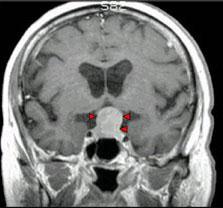

问题 男,37岁,视力模糊,部分视野缺失,伴有头痛、恶心数月,MRI检查如图,最可能的诊断为()

选项 A.颅咽管瘤 B.脑膜瘤 C.蛛网膜囊肿 D.垂体瘤 E.表皮样囊肿

答案 D